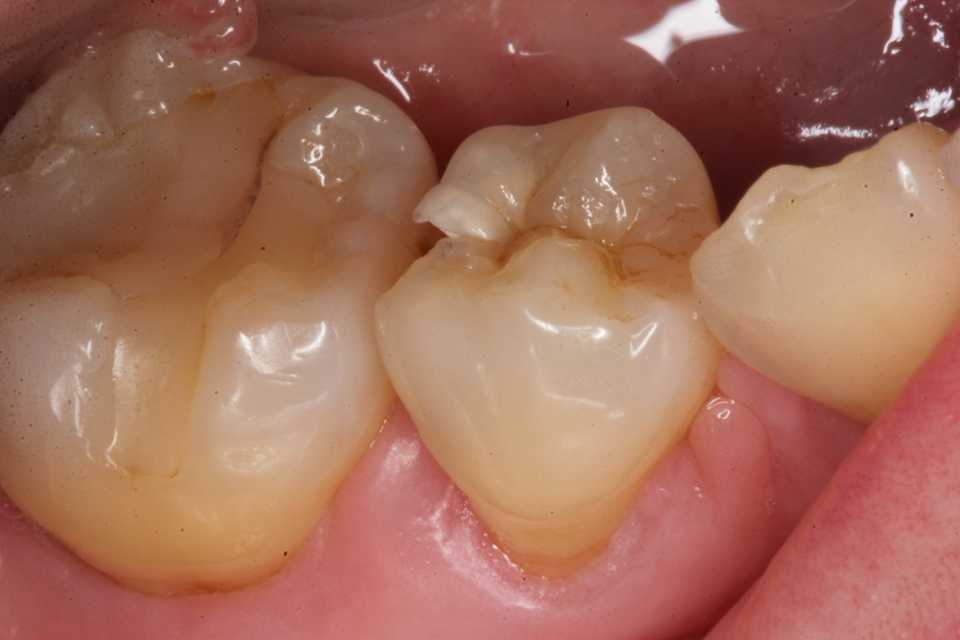

40代女性、右上345、外傷性カリエス、自発痛+ちょっと目を離すと虫歯になり、痛いです。。とやってくる。歯ぎしり食いしばりがあるので、ナイトガードを作ってはいるのだが、鬱陶しいとかでサボっている。標準治療では痛みがあれば神経を取って冠を被せることになるのだが、本人はそんなことは知らない。うちに来れば1回で治るので大したことはないと気にしていない。今日は痛みの出ている右上5を主に処置する。僕が使っているボンディング材はこちら。α-TCPに3MIXを耳かき一杯添加し、50%クエン酸で練る。この上からCRダイレクトボンディングでカバーする。3MIXの作り方はこちら。α-TCPの入手法はこちらでは時系列でどうぞα-TCPの製造元を公開した所為か、α-TCPの入手性が良くなっているように感じる。少しずつここの治療法が広まってくれると嬉しいのだが。ここからは実際のCRでの再建なのだが、使用する材料や器具もなんでも良いというわけではないと思う。ここのFreepage list を参照して欲しい。ここで使っている材料器具は全て公開している。ストリップス(隔壁)を使わずに隣接面窩洞のCR充填(というよりは修復)ができるというのは常識外の話で、一般の歯科医師はやってみたことも考えたこともないとは思う。そもそも歯学部では習わないからだと思う。しかしできないことはなく、辺縁漏洩も気泡が入ることもないので長期的に予後は良好となる。